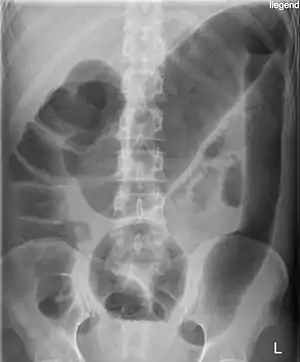

![]() Рентгенологічний знімок токсичного мегаколона при виразковому коліті. Рентгенологічний знімок токсичного мегаколона при виразковому коліті. | |

Діагностика проводиться первинно за допомогою рентгенографії живота. Можливе також використання комп'ютерної томографії.